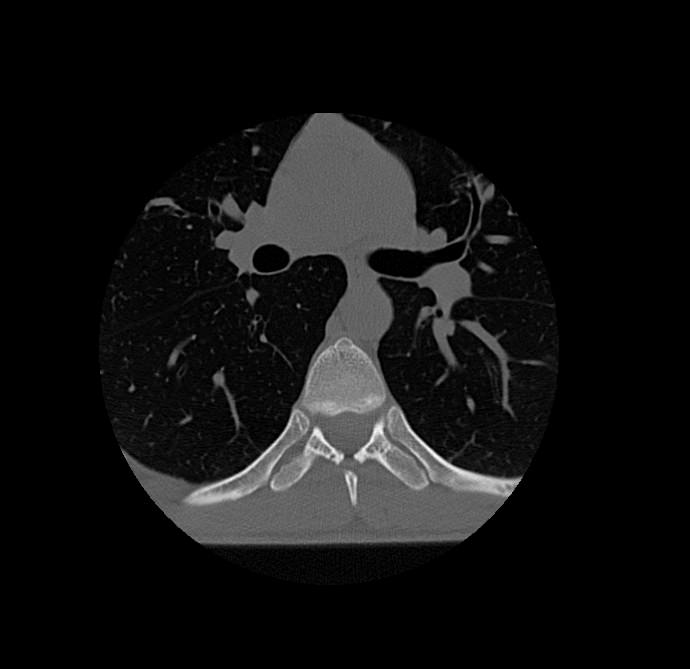

Мультиспиральная компьютерная томография – это современный быстрый и точный способ диагностики заболеваний позвоночника, основанный на использовании рентгеновского излучения. Метод позволяет получать послойные изображения грудного сегмента позвоночного столба, включая 12 грудных позвонков, задние отрезки ребер, межпозвоночные диски, позвоночный канал.

При помощи инновационных компьютерных программ данные преобразуются в трехмерные изображения позвоночного столба с сосудами, нервами и лимфатическими узлами в мельчайших подробностях. Наглядные объемные 3D-изображения высокого качества помогают в диагностике различных заболеваний позвоночника и бывают особенно полезны при планировании хирургических операций, при оценке эффективности проведенного лечения.

Что показывает компьютерная томография грудного отдела позвоночника

- изменения структуры и расположения позвонков и окружающего их мышечно-связочного аппарата

- аномалии развития позвоночника

- травмы позвоночного столба (переломы и трещины)

- ширину спинномозгового канала

- признаки наличия межпозвоночной грыжи (протрузии, экструзии)

- абсцессы, туберкулёзное поражение, новообразования, наличие метастазов и прорастание опухолей из соседних органов

- изменения в спинном мозге (кровоизлияния и др.)

- дегенеративные изменения

- участки пониженной плотности кости — остеопороз при визуальной оценке